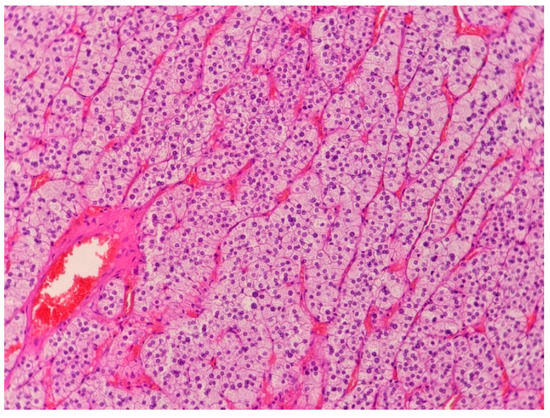

2.1. Case 1

2.2. Case 2

2.3. Case 3

2.4. Case 4

2.5. Case 5

2.6. Case 6

2.7. Case 7